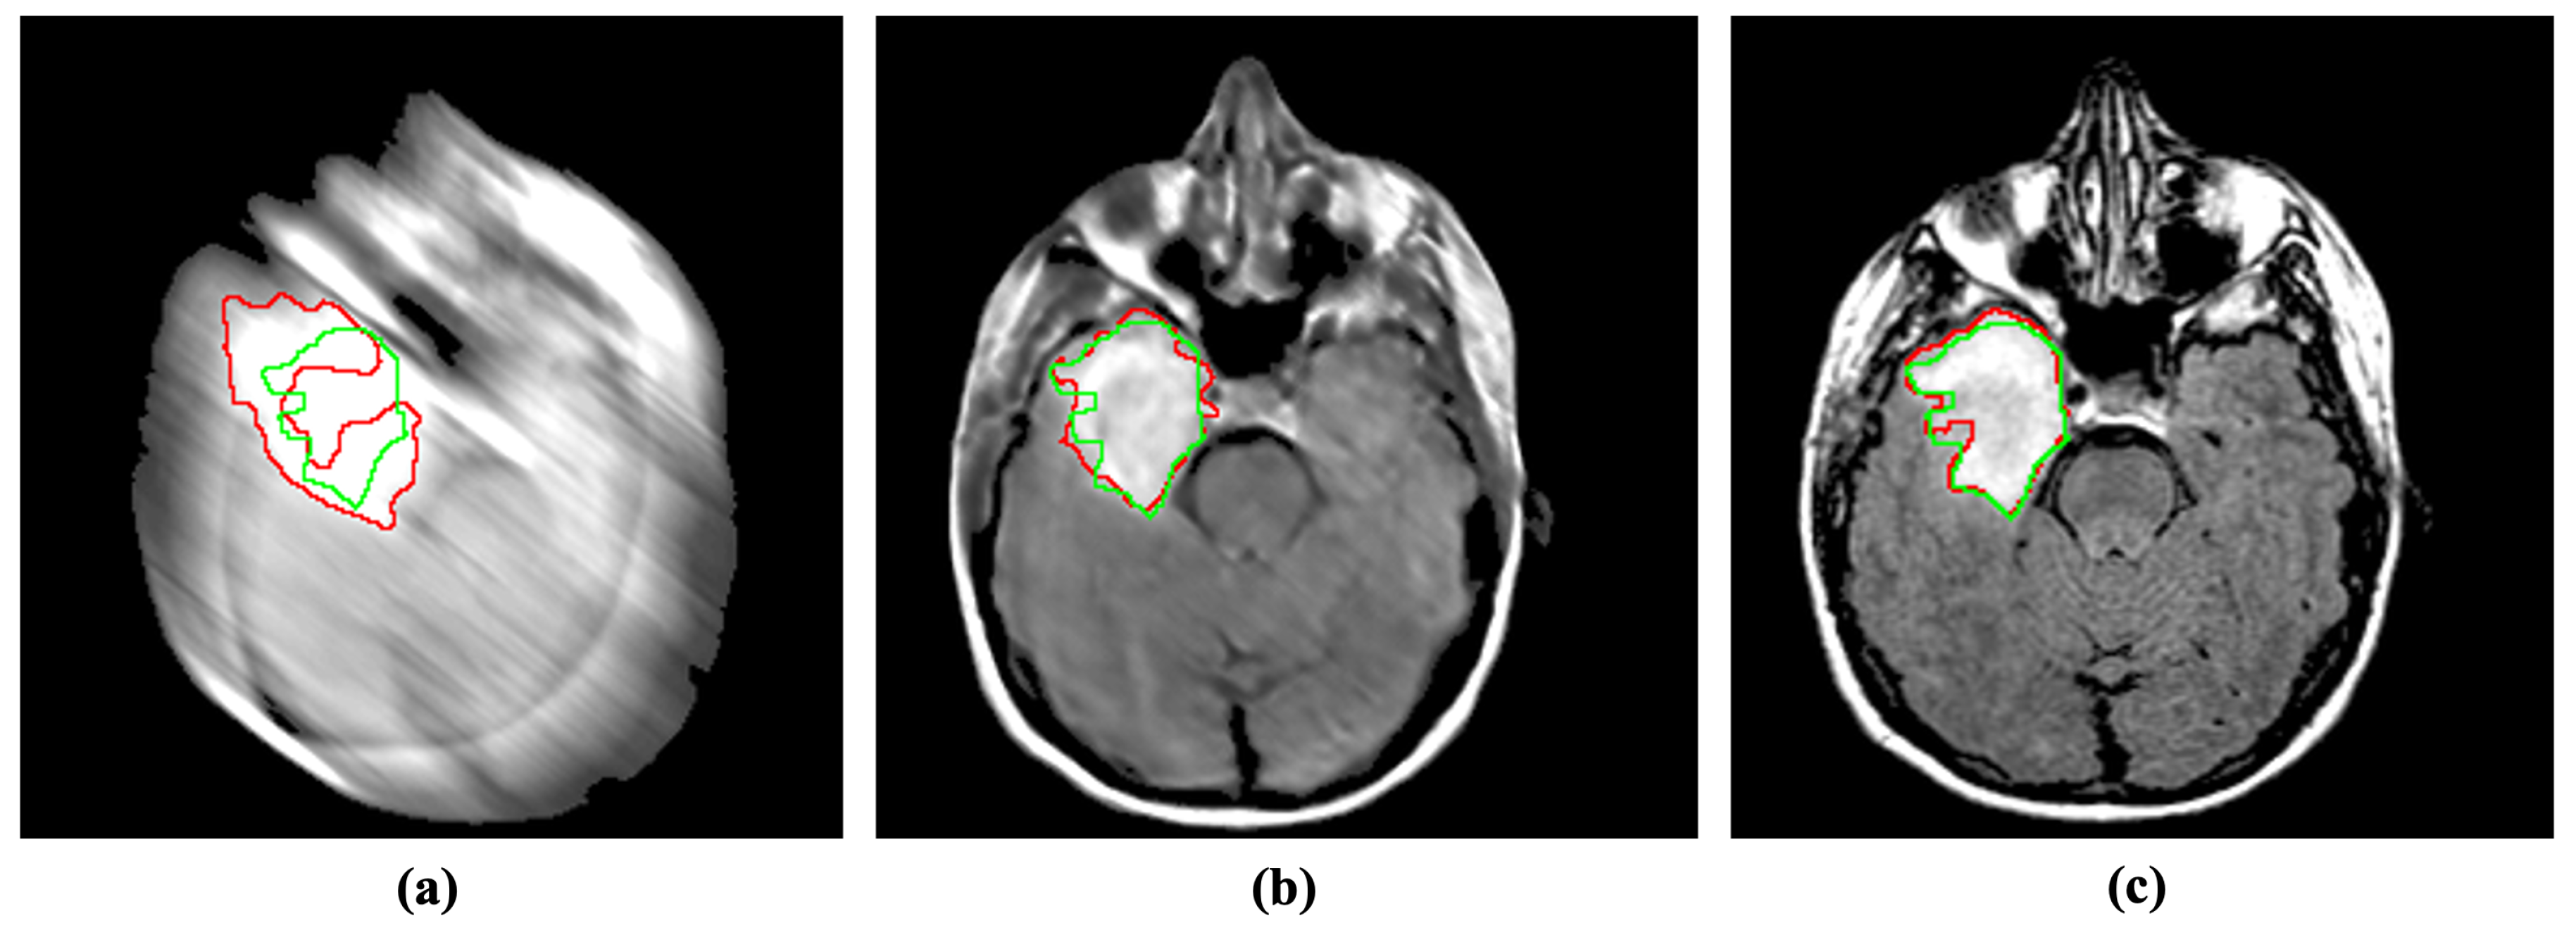

Abnormality segmentation is considered among the most prominent CAD applications in medical image analysis. Despite having substantial real-world implications, medical image segmentation suffers from blind-motion blur. As Figure 6 illustrates, the existing segmentation methods’ performance can drastically deteriorate by blind-motion blur. A robust deblurring method can help segmentation methods in improving their performance. Here, we evaluated the SOTA U-net architecture inspecting the impact of blurs in segmentation on MRI images.

Figure 6.

Incorporating the proposed method for deblurring medical images can improve medical image segmentation performance. The red and green regions represent the area segmented by the deep model and the actual (ground-truth) affected region. (a) Blurry image + U-Net [36]. (b) Deblurred image obtained by proposed method + U-Net [36]. (c) Reference image + U-Net [36].